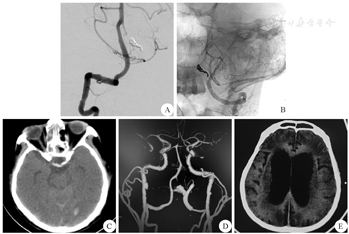

患者 男性,50岁,因"头痛、呕吐3 d,突发意识丧失4 h"于2022年5月16日就诊于我科。入院体检:神志昏迷,格拉斯哥昏迷量表(GCS)评分5分,Hunt-Hess分级Ⅲ级。双侧瞳孔等大等圆,直径约为3 mm,对光反射迟钝。体温36.4 ℃,血压142/72 mmHg(1 mmHg=0.133 kPa),心率103次/min,血氧饱和度(SPO2)96%。颅脑CT检查示:广泛蛛网膜下腔出血,脑室内少量积血,脑实质密度减低,灰白质分界不清,脑沟裂池见广泛铸形高密度(图1A)。颅脑CTA检查示:左侧椎动脉见梭形瘤样增粗,大小约13.4 mm×5.1 mm;左侧颈内动脉C1段瘤样小突起,瘤颈宽约3.8 mm,瘤体大小约3.2 mm×2.4 mm(图1B)。

A:术前CT;B:术前CTA;C:术中DSA

诊断:考虑为急性破裂期椎动脉夹层动脉瘤。拟行急诊Pipeline密网支架辅助弹簧圈栓塞椎动脉夹层动脉瘤术,术前予以胃管顿服阿司匹林(300 mg)和硫酸氢氯吡格雷片(300 mg)。患者全身麻醉后使用Seldinger技术穿刺右侧股动脉,并置入6F动脉鞘;在全身肝素化状态下,使用5F单弯造影管,对患侧椎动脉行3D脑血管造影,发现左侧PICA以远处椎动脉闭塞,PICA及其近端椎动脉亦有夹层形成,最终考虑为累及PICA的椎动脉夹层动脉瘤(图1C)。在5F普微森中间导管的导引下,将6F/70 cm长鞘送至左侧椎动脉开口,5F普微森中间导管上至左侧椎动脉;接下来选取Echelon-10微导管,尖端塑形后超选至左侧椎动脉夹层动脉瘤内,然后通过Echelon-10微导管行动脉瘤介入栓塞,向左侧椎动脉瘤内填入大小不同的弹簧圈共计3枚,造影提示左侧椎动脉夹层动脉瘤不显影。将Marksman支架微导管置于左侧PICA远端,并缓慢释放Pipeline密网支架(美国美敦力公司,3 mm×20 mm),支架头端置于PICA近端,末端于左侧PICA近端椎动脉处完全释放。术后即刻行脑血管造影,提示左侧PICA以远椎动脉瘤不显影,左侧PICA显影良好;右侧椎动脉造影提示左侧脊髓前动脉供血良好(图2A),弹簧圈栓塞致密,Pipeline密网支架位置良好(图2B)。术后予继续口服双联抗血小板聚集药物(阿司匹林100 mg/d,硫酸氢氯吡格雷75 mg/d),行腰椎穿刺术释放血性脑脊液。术后1周复查头颅CT提示:蛛网膜下腔及脑室内积血进一步吸收(图2C)。患者症状较术前有好转。随访至术后4个月,患者GCS评分为7分。术后4个月复查颅脑CTA示左侧PICA显影欠佳(图2D),术后6个月复查颅脑CT示明显脑积水(图2E),考虑Pipeline密网支架对PICA血流通畅性造成影响。

A:B:术后即刻三维DSA;C:术后1周时颅脑CT;D:术后4个月时颅脑CTA;E:术后6个月时颅脑CT